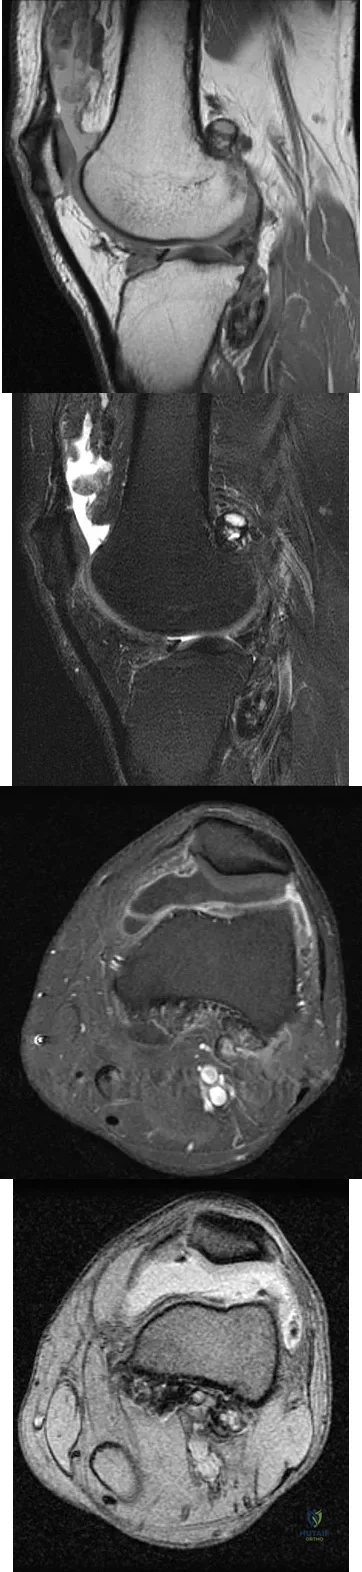

A 28-year-old man reports knee stiffness, swelling, and a constant ache that is worse with activity. Examination reveals an effusion, global tenderness, and warmth to the touch. Flexion is limited to 110 degrees. Figures 48a through 48d show sagittal T1-weighted, sagittal T2-weighted, axial T1-weighted fat-saturated gadolinium, and axial gradient echo MRI scans. Based on these findings, what is the most likely diagnosis?

Explanation